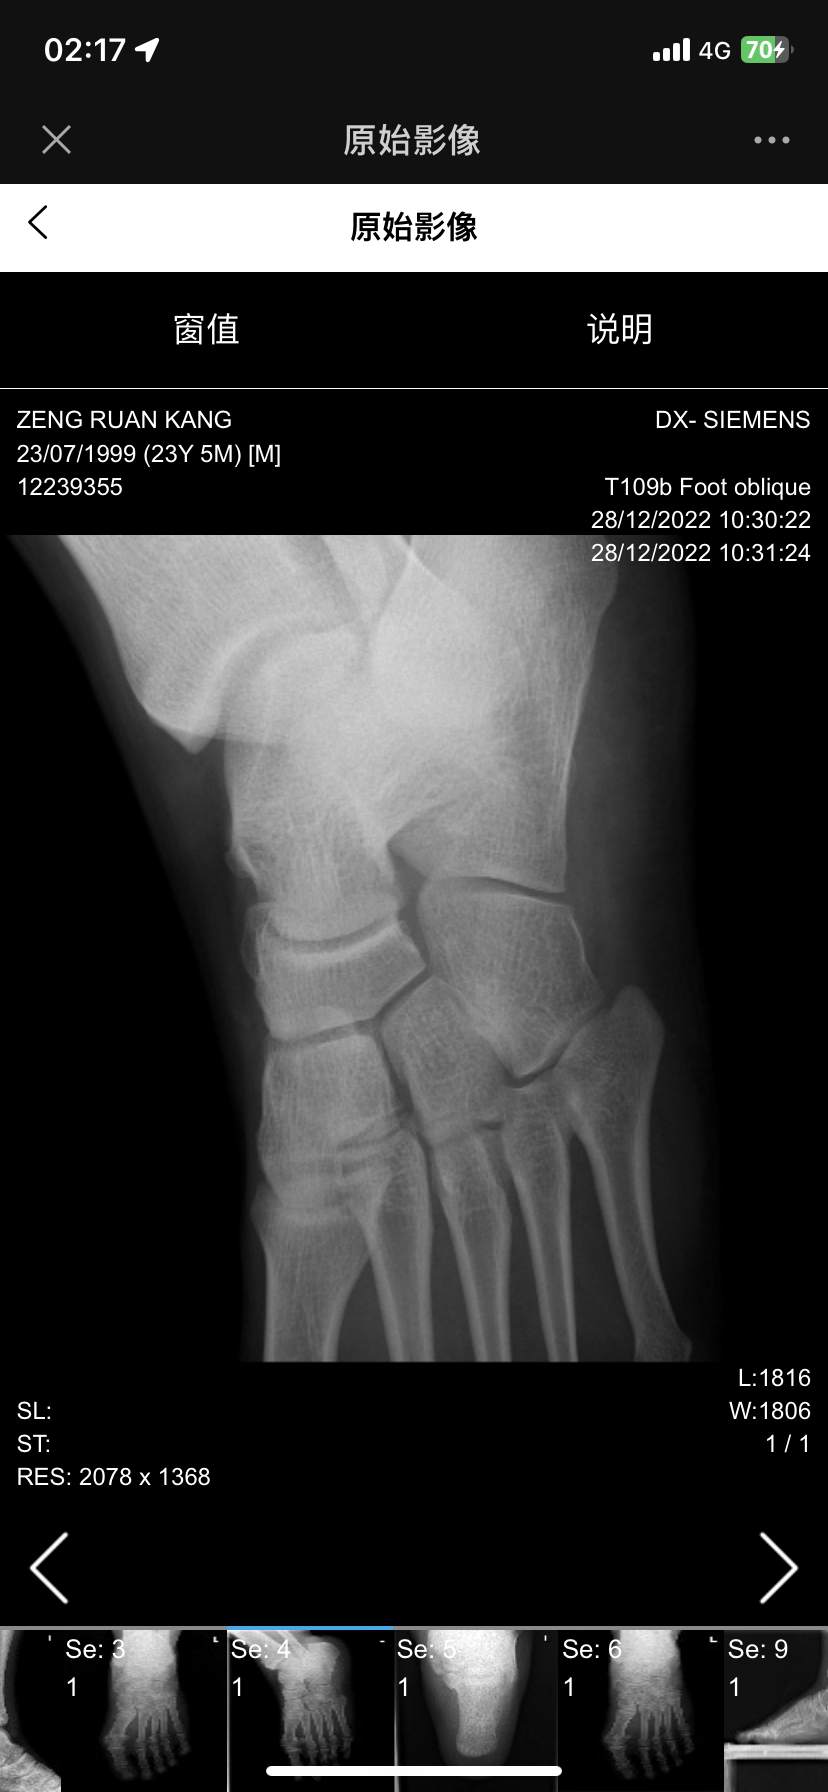

扭伤后组底外侧跟骰关节处疼痛五年,骰骨综合征?

患者五年前跖屈内翻扭伤,痊愈后才注意到足底外侧骰骨处疼痛,行走时尤甚,随着活动增加而加重,这几年找了很多足踝大夫都看不出来,因为b超磁共振和x光没有显示任何结构问题,也没有炎症水肿的表现,活动度也基本正常,内外翻跖屈背曲无痛,尝试过药物,封闭,针刀,冲击波等效果均不佳,因疼痛影响生活轻度抑郁,老师们考虑这是什么病?